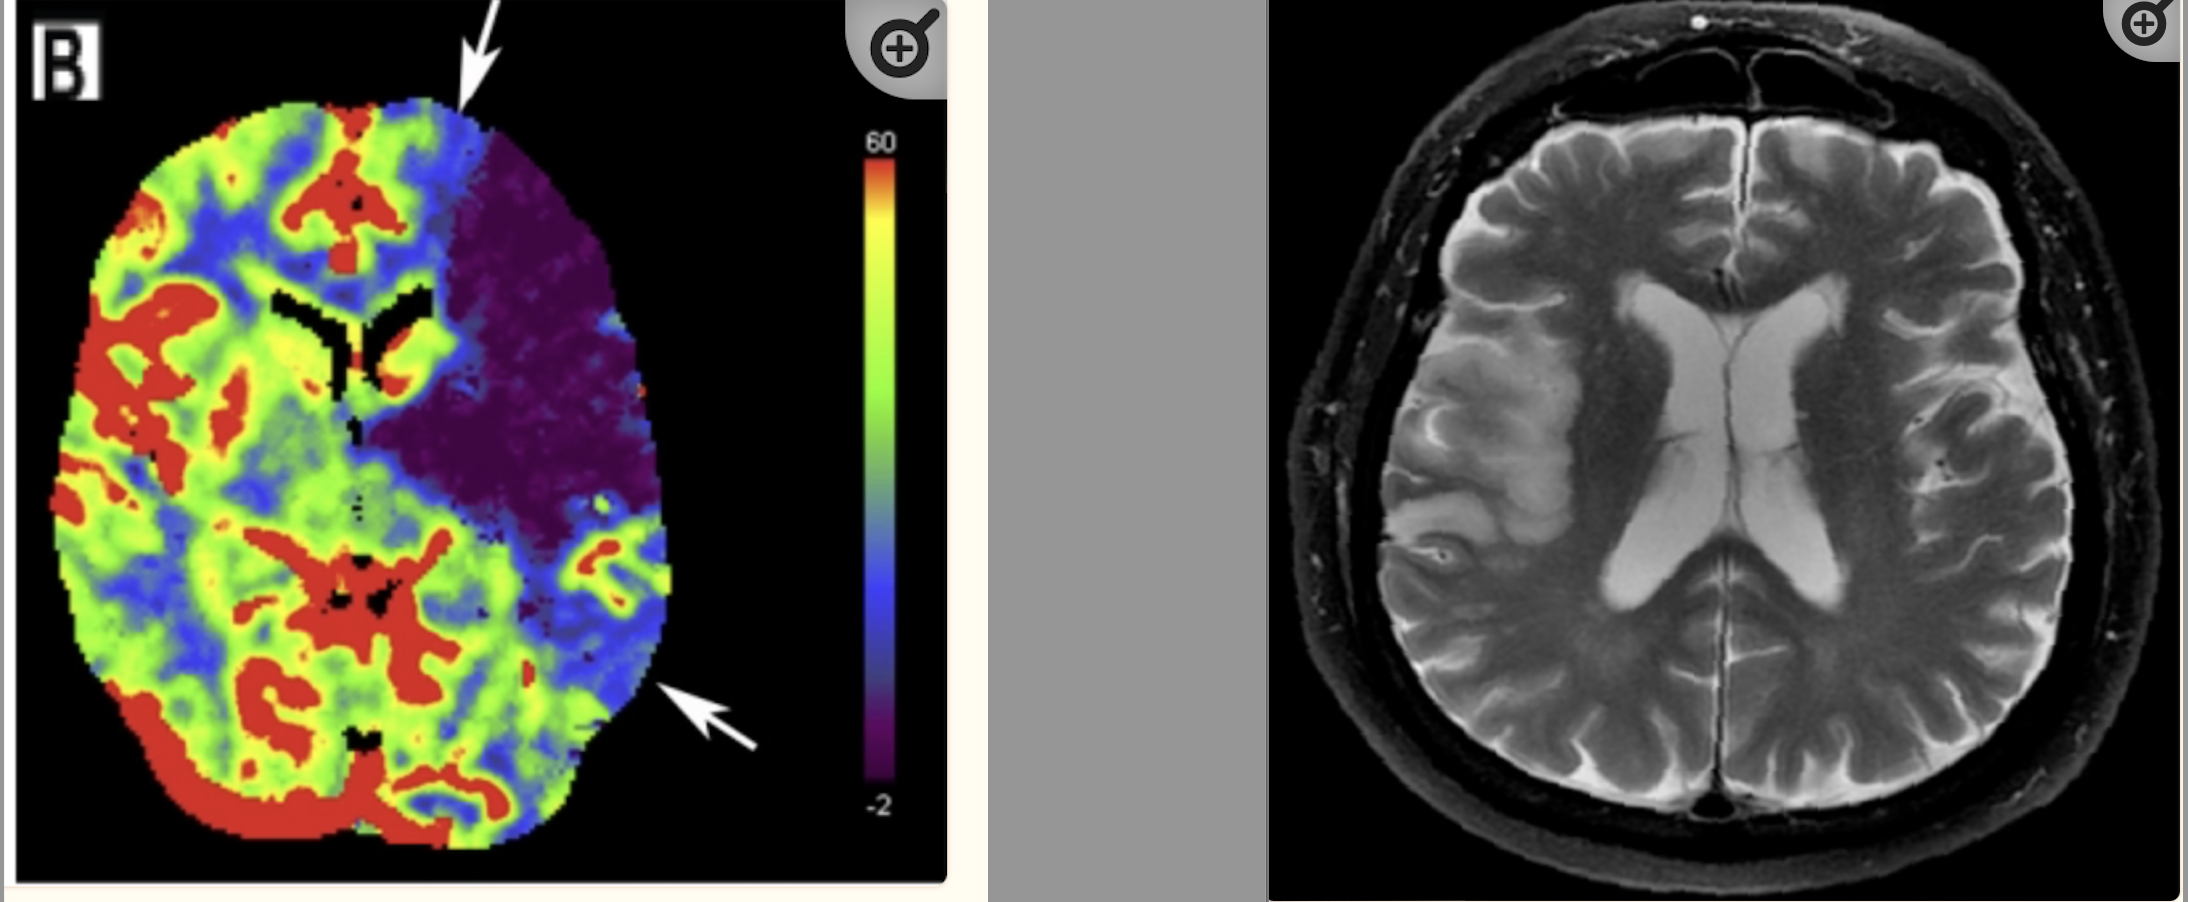

For example, a patient presenting with chest pain has findings on a chest x-ray that that could be pneumonia or pulmonary edema. Should they be treated for both, either, or neither? Or as another example, a patient with vague abdominal pain, a non-specific physical exam, and normal labs has a CT scan of the abdomen which shows findings of an adrenal mass or a marginally dilated appendix. Is the marginally dilated appendix the source of her symptoms? Should she be referred to the general surgeon for the marginally dilated appendix? What does adrenal mass mean for this patient? Does it require surveillance? Or the known scourge to the ED physician – the elderly patient with the interoceptive sensation of “dizziness.” Exam findings in such patients are reliably unreliable. Essentially grasping for security, the ED physician reaches for CT imaging to rule-out a high-morbidity diagnosis such as a brain hemorrhage, but knows full well that the test is insensitive to an ischemic stroke or a transient ischemic attack (TIA). If the CT happens to be normal and even if symptoms normalize, is the patient safe for discharge when neither an ischemic stroke or TIA is ruled-out?